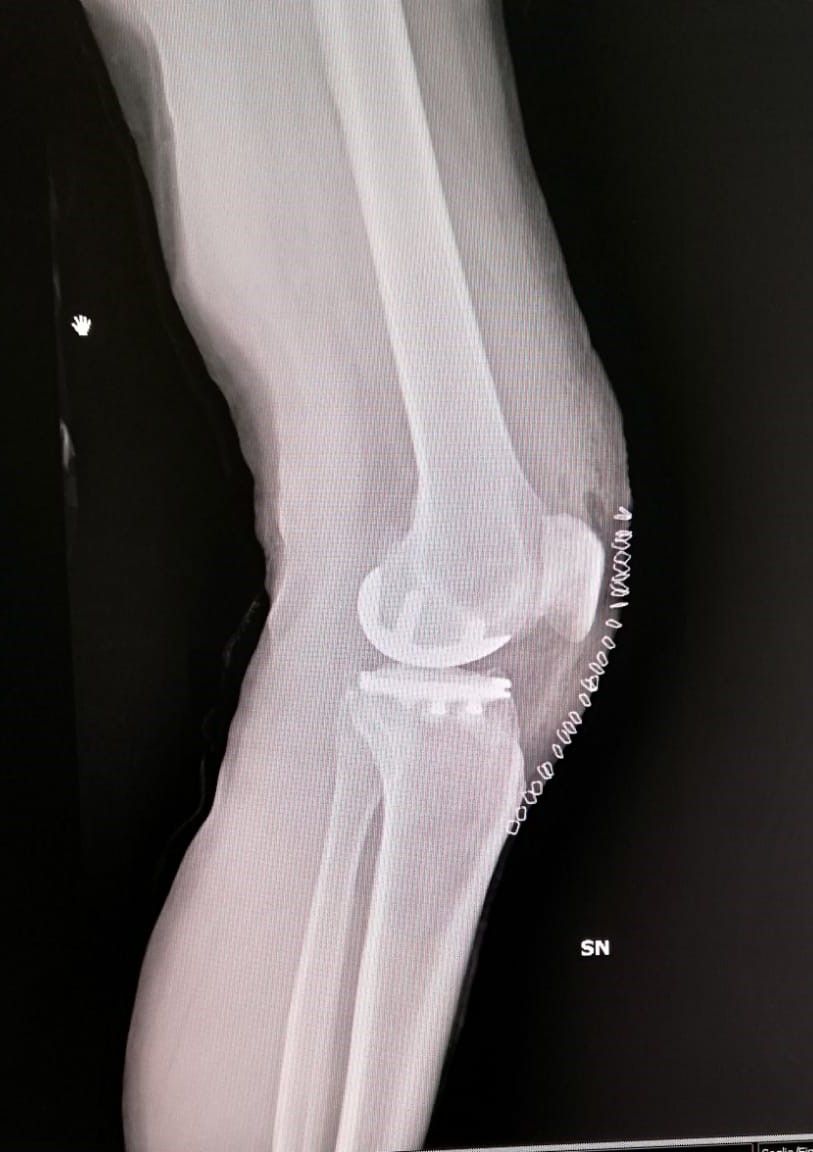

- protesi totale di ginocchio

- protesi mono-compartimentale del ginocchio

Dopo due anni di tentativi vani e aver consultato vari ortopedici, finalmente il dr.Zornetta mi ha illustrato bene la situazione del mio ginocchio. Persona che subito ti trasmette fiducia, competenza e finalmente ti spiega con chiarezza cosa hai, che dire e' una persona semplice e simpatica. Cosi' dopo gli ultimi esami mi ha consigliato l intervento al ginocchio con mezza protesi, mi sono fidata di lui anche perche' mi avrebbe operata lui stesso. A me e' andata tutto bene e lo ringrazio!

Medico competente e preparato, presente durante il ricovero e successivamente, nel mio caso protesi ginocchio. Disponibile e gentile. Esperienza positiva.

Il dottor Zornetta mi ha spiegato molto chiaramente tutti i punti che hanno portato alle operazioni per le protesi a entrambe le ginocchia. Presente anche nel post operazione. Sono molto contenta dei risultati e consiglio vivamente questo dottore.

Ottimo ortopedico,ti segue sino alla fine della operazione e oltre.quando hai bisogno,c'è.ho fatto 2 protesi ai ginocchi da lui.